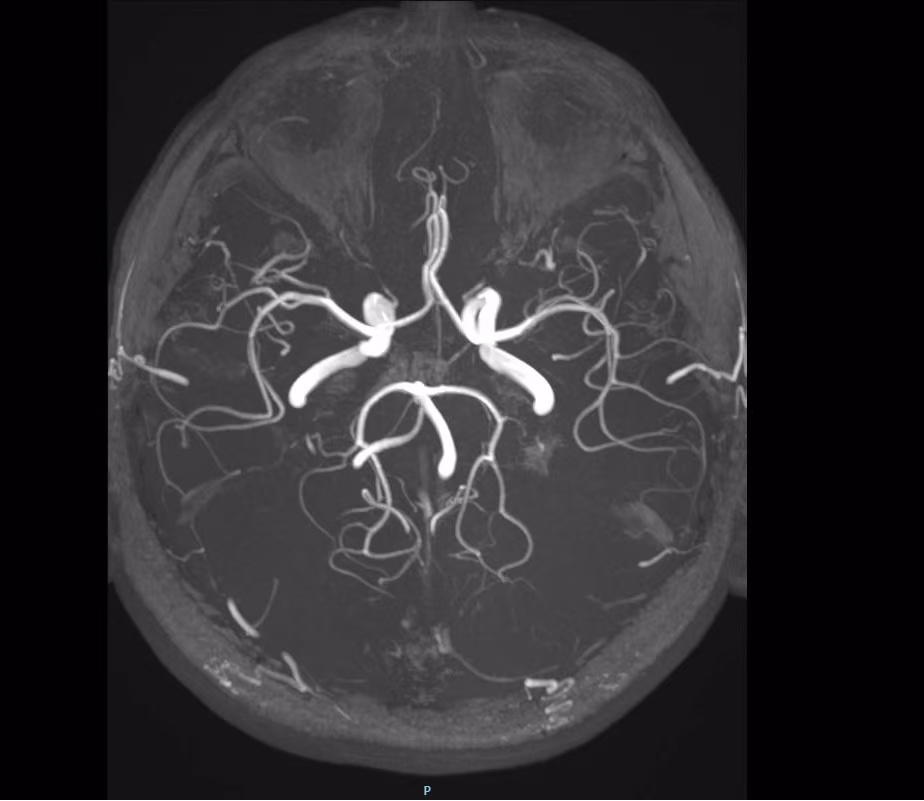

椎动脉